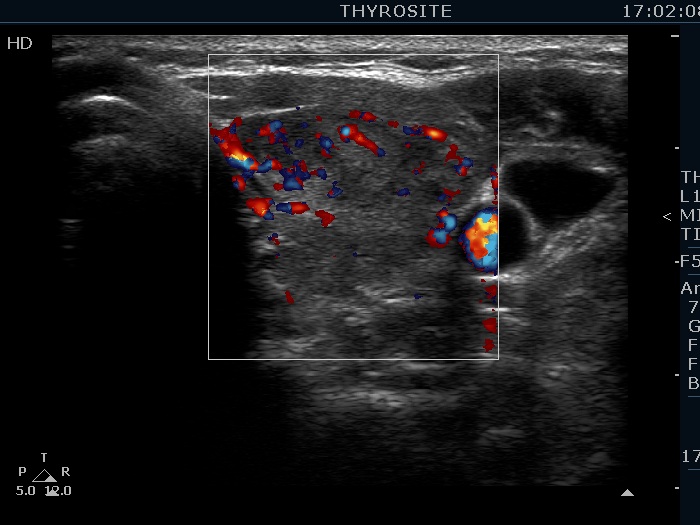

Lymphocytic thyroiditis - case 786 (ultrasonographic picture 6)

Left lobe, transverse scan, color Doppler mode. The vascularity is a bit increased.